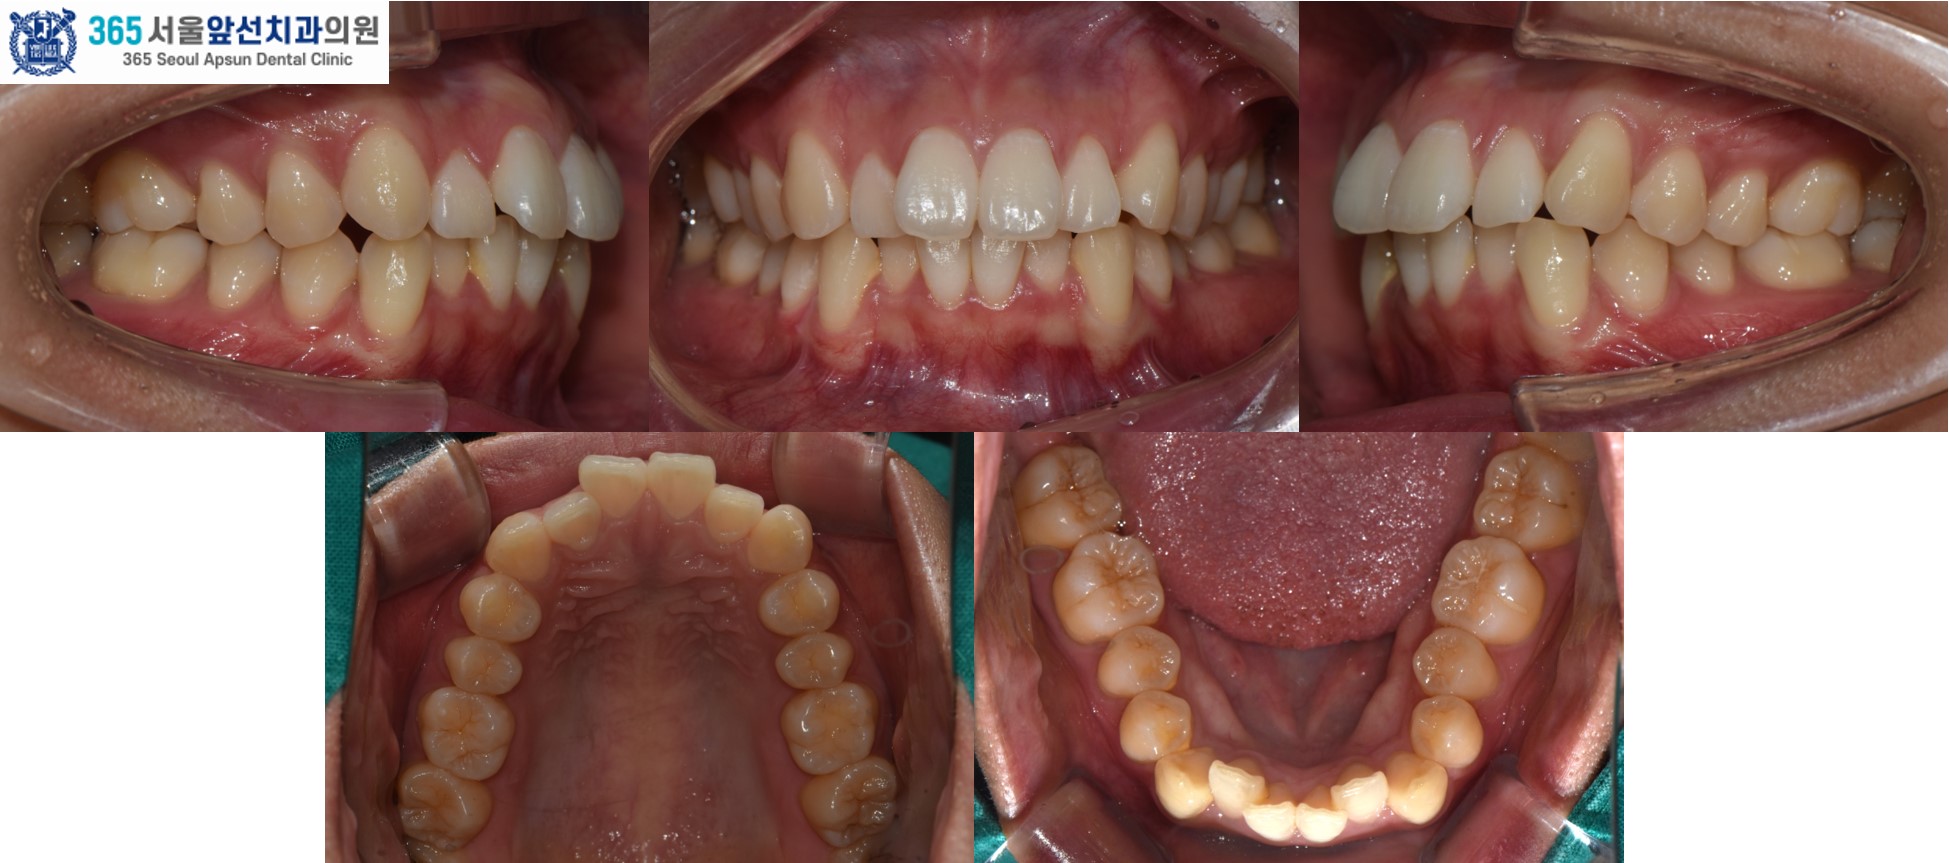

앞니의 비뚤한 치열을 고민으로 내원하신 20대 여성 환자 분의 증례를 소개드리겠습니다. 치료 전의 모습입니다. 상,하악 치열 각각 3.1mm, 2.9mm 의 필요 공간이 있는 중등도의 총생(Crowding)이 관찰됩니다. (그림2) 촬영일자 2025.02.25.

아랫니의 치열이 윗니의 치열보다 후퇴되어있는 2급 부정교합도 있었지만, 환자분은 2급 부정교합은 수정하지 않고 앞니의 치열만 가지런히 하기를 원하셔서 부분 교정으로 진행하였습니다. 이 경우, 2급 부정교합과 수평 피개는 잔존하게 됩니다. 부정교합의 정도에 따라, 치료계획을 좀더 간단하게 수정할 수 있습니다. 전체 교정과 부분 교정의 계획은 꼭 전문의와의 상담을 통해 결정하는 것이 좋습니다. ^^ (그림3) 촬영일자 2025.11.06.